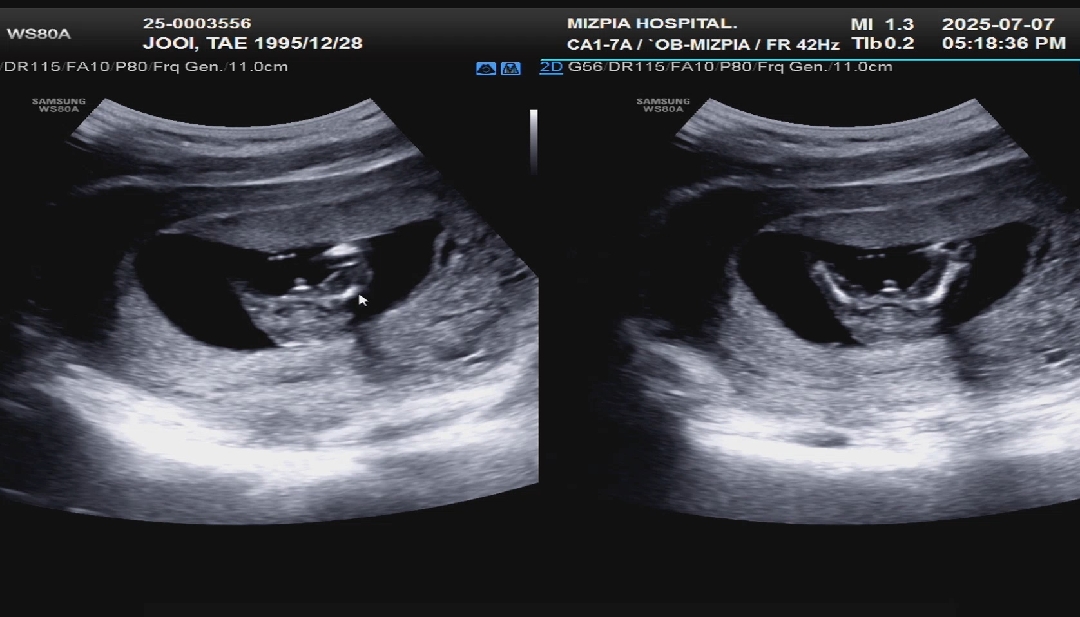

14주 0일 성별반전 없을까요ᆢ?

오늘 너무 머리아프고 해서 촘파보러갔다가 아가가 다리를 좌악 벌리고있어서 얼결에 가랭이 직관했는데 왜 뭐가 있죠ᆢ? 매끈해야되는데ᆢ? ㅠㅠㅠ 반전 없을까요ㅜㅜㅜㅜㅜ

ㅠㅠㅠㅠㅠ너무 존재감이 확실한가요ㅠ

아들 둘맘으로써.... 초음파에 고츄모양이확실해요..ㅋㅋ